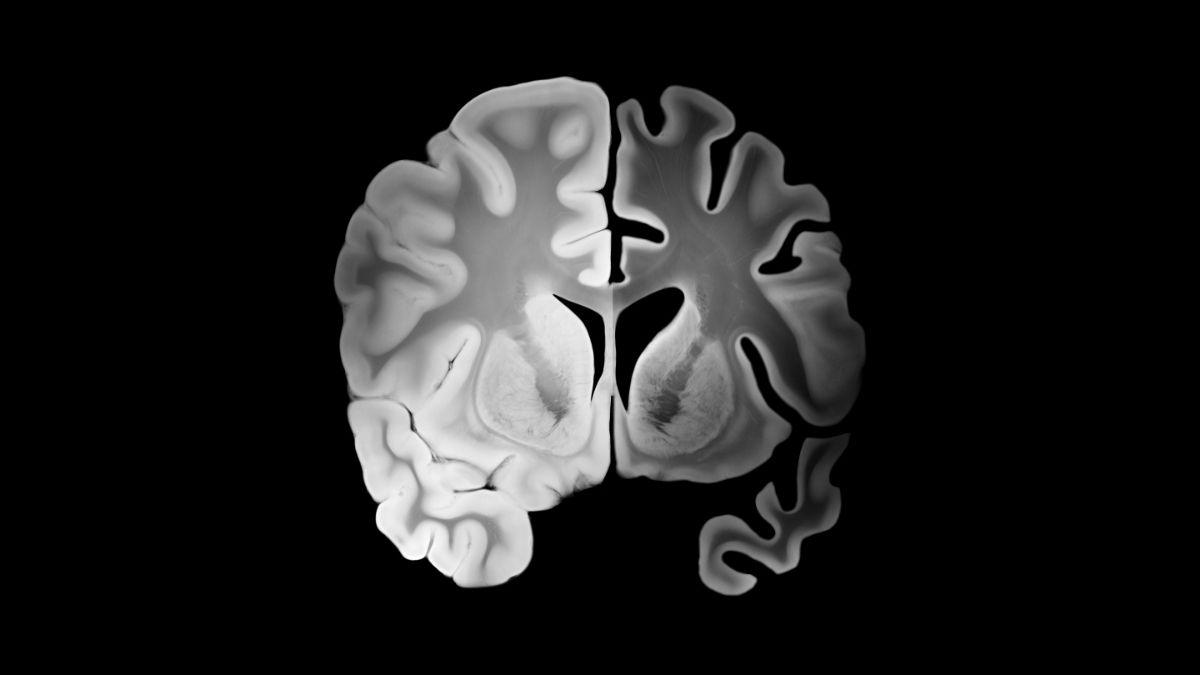

Ahora, un equipo con participación catalana ha dado un paso que suena casi a ciencia ficción. Han conseguido revertir los síntomas del Alzheimer en ratones… y lo han hecho en un tiempo sorprendentemente corto. El secreto no ha estado en actuar directamente sobre las neuronas, como suele ser habitual, sino en algo que hasta ahora había pasado más desapercibido. El protagonista de esta historia es el sistema vascular del cerebro.

En lugar de eso, los científicos se centraron en restaurar el buen funcionamiento de la barrera hematoencefálica. Este sistema es como un filtro que separa el cerebro de la sangre. Lo protege de toxinas, patógenos y sustancias dañinas. En el Alzheimer, esa barrera también falla. Uno de los problemas clave es que el cerebro pierde eficacia para eliminar la proteína beta-amiloide, un residuo tóxico que se acumula y daña el funcionamiento neuronal.

La clave está en los vasos sanguíneos del cerebro

El estudio refuerza una idea cada vez más presente en la investigación sobre demencias: la salud vascular es crucial.